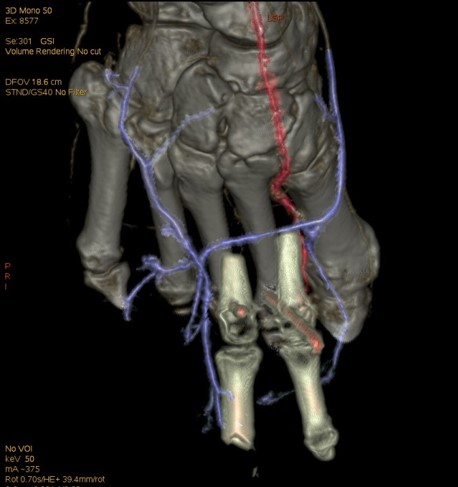

右足寄养皮瓣血管状况

选择50keV进行寄养动脉观察